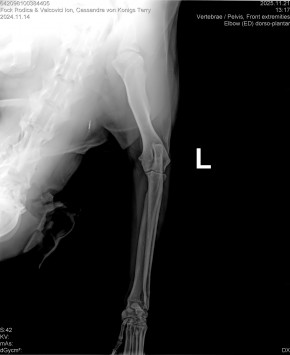

CASSANDRA VON KONIGS-TERRY

( CASSY )

Data nasterii:

14.11.2024

Crescator:

FOCK RODICA si VALCOVICI ION